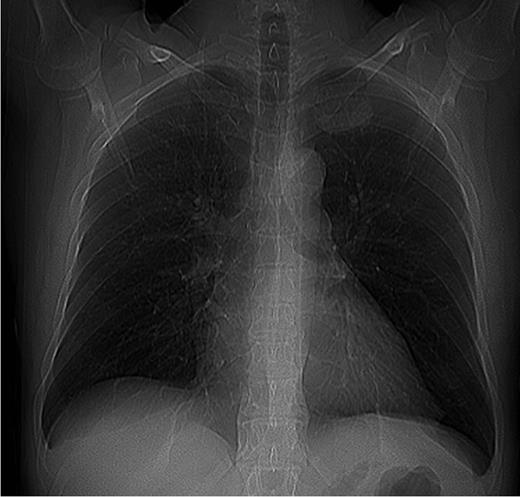

However, chest X-ray should be performed as first step when IMAA is suspected. An additional CT scan conceivably in combination with an angiography is a valuable method to localize the IMAA and to plan the surgical procedure [1]. In our patient, classical symptoms of an IMAA were missing and the IMAA was an incidental finding within routine X-ray. The compression symptoms of the IMAA were only found after accurate request and examination. The additional imaging procedures failed to confirm the diagnosis.